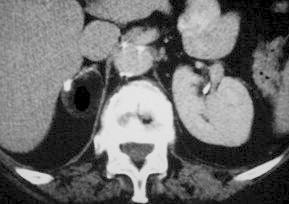

We reviewed 45 articles, that confirmed, with a high level of evidence-based medicine, that the diagnosis of a lipomatous adrenal tumour is made by various imaging procedures, particularly computed tomography (CT). We emphasise the importance to their management of the initial size of the adrenal mass, its increase in size over time, in addition to the presence of symptoms.

Lipomatous tumours of the adrenals are most frequently benign. The diagnosis is usually made by various techniques, in particular CT. The fundamental characteristics indicating the necessity of surgical intervention are the symptoms presented, volume of the tumoral mass (>5 cm), and the increase in size of the tumour as shown in two consecutive imaging studies.

我们回顾了45篇文章,这些文章以高水平的循证医学证实,肾上腺脂肪瘤的诊断可通过多种影像学检查,尤其是计算机断层扫描(CT)。我们强调肾上腺肿块的初始大小、其随时间的增大以及症状的存在对其治疗的重要性。

肾上腺脂肪瘤大多为良性。诊断通常通过多种技术,尤其是CT做出。表明需要手术干预的基本特征是出现的症状、肿瘤肿块的大小(>5厘米)以及连续两次影像学检查显示的肿瘤增大。